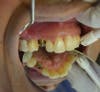

Dental implants have become a common solution for missing teeth. Where bridges had been the standard of care for a missing teeth only a few years ago, they are no longer recommended.

The teeth on either side of a missing tooth receive additional stress when they become the anchor teeth for a bridge. These teeth have the luxury of standing alone when an implant is placed.